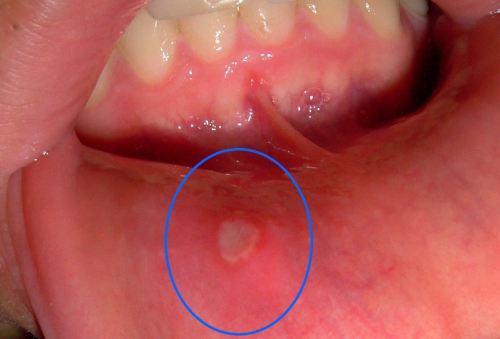

Aftas

As aftas não são contagiosas. E é importante diferenciá-las das lesões provocadas pelo herpes. No entanto, provocam dor e ardor, e pioram quando se ingere alimentos quentes ou picantes, atrapalhando atividades do dia a dia, como falar e comer. A maioria das aftas dura em média de 1 a 2 semanas e costuma curar sem deixar cicatriz.

Os medicamentos disponíveis para seu tratamento visam diminuir sua freqüência e aliviar seus sintomas. Os mais utilizados são corticóides em forma de pomadas, de uso tópico, ou seja, aplicados no local. Melhorar a higiene bucal também auxilia no tratamento das aftas. Por isso, em alguns casos, são utilizados enxaguatórios bucais com clorexidina e antissépticos, diminuindo as bactérias presentes na cavidade oral.

Em casos mais graves, corticóides na forma de comprimidos podem ser utilizados, até por serem muito eficazes. Os antiinflamatórios também podem ser utilizados no alívio da dor. É importante observar que, caso as aftas persistam por mais de 14 dias, caso elas sejam muito grandes, se houver febre ou se aparecerem com freqüência, deve-se procurar a orientação de um dentista para um diagnóstico mais preciso. Em alguns casos, poderá ser necessário realizar um procedimento que passará por uma biópsia e que será enviada para um laboratório de anatomia patológica.